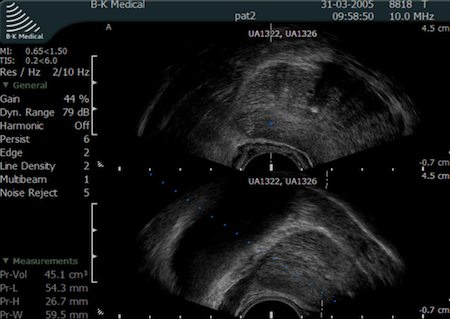

Aby urolog mógł obejrzeć strukturę gruczołu krokowego na ekranie aparatu USG konieczne jest włożenie głowicy transrektalnej do odbytnicy. Głowica transrektalna jest specjalną głowicą USG podobną do tych stosowanych w badaniach ginekologicznych.

Głowica transrektalna w swoim korpusie ma wbudowany kanał biopsyjny, przez który urolog wprowadza igłę TRUCUT. Igła TRUCUT jest specjalnie zaprojektowaną igłą, która umożliwia precyzyjne pobranie wycinków z gruczołu krokowego pod kontrolą obrazu oglądanego na monitorze aparatu USG.

Fot. Widok gruczołu krokowego w badaniu TRUS podczas biopsji stercza.

Pacjent podczas biopsji ułożony jest na lewym boku. Przed przystąpieniem do biopsji stercza lekarz wykonuje badanie per rectum - polegające na ocenie stercza palcem przez odbytnicę. Kolejnym etapem badania jest wprowadzenie głowicy transrektalnej do odbytnicy. Przed pobraniem wycinków z prostaty urolog wykonuje USG transrektalne, oceniając gruczoł krokowy.